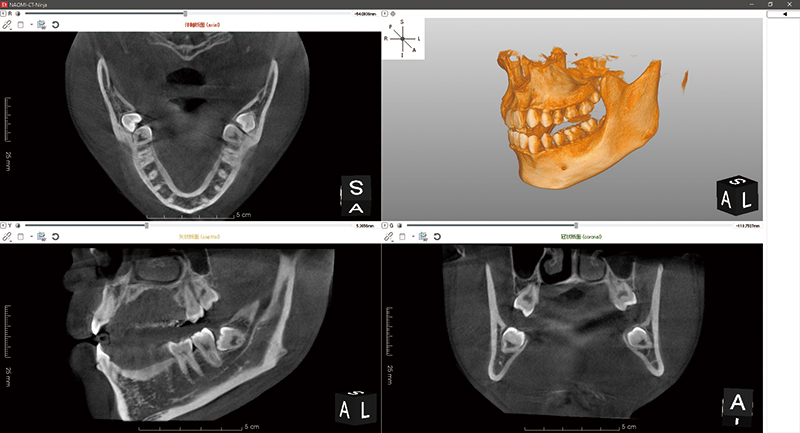

CTとはコンピューター断層撮影(Computed Tomography)の略称です。

解析したい部位を細かく輪切りにし、それぞれの断面の画像を撮影する技術です。

歯科用CTでは、歯が失われた部分の骨の幅や深さや骨質、下顎管や上顎洞までの距離を正確に測定することができます。

今までのDentalX線やパノラマX線では2次元の情報しか得ることができなかったのが、歯科用CTで撮影することにより3次元の情報を得られるため、より正確な診断が可能になります。

当院ではインプラントの他、親知らずの抜歯や根管治療、歯周病の治療などに用いています。

インプラント治療においては下顎管や上顎洞の位置関係、骨の幅や深さ、骨質等をきちんと把握することにより、手術時のリスクをを軽減させることができます。 またインプラントの埋め込み位置や挿入深さの決定や患者様への説明にも必要となります。